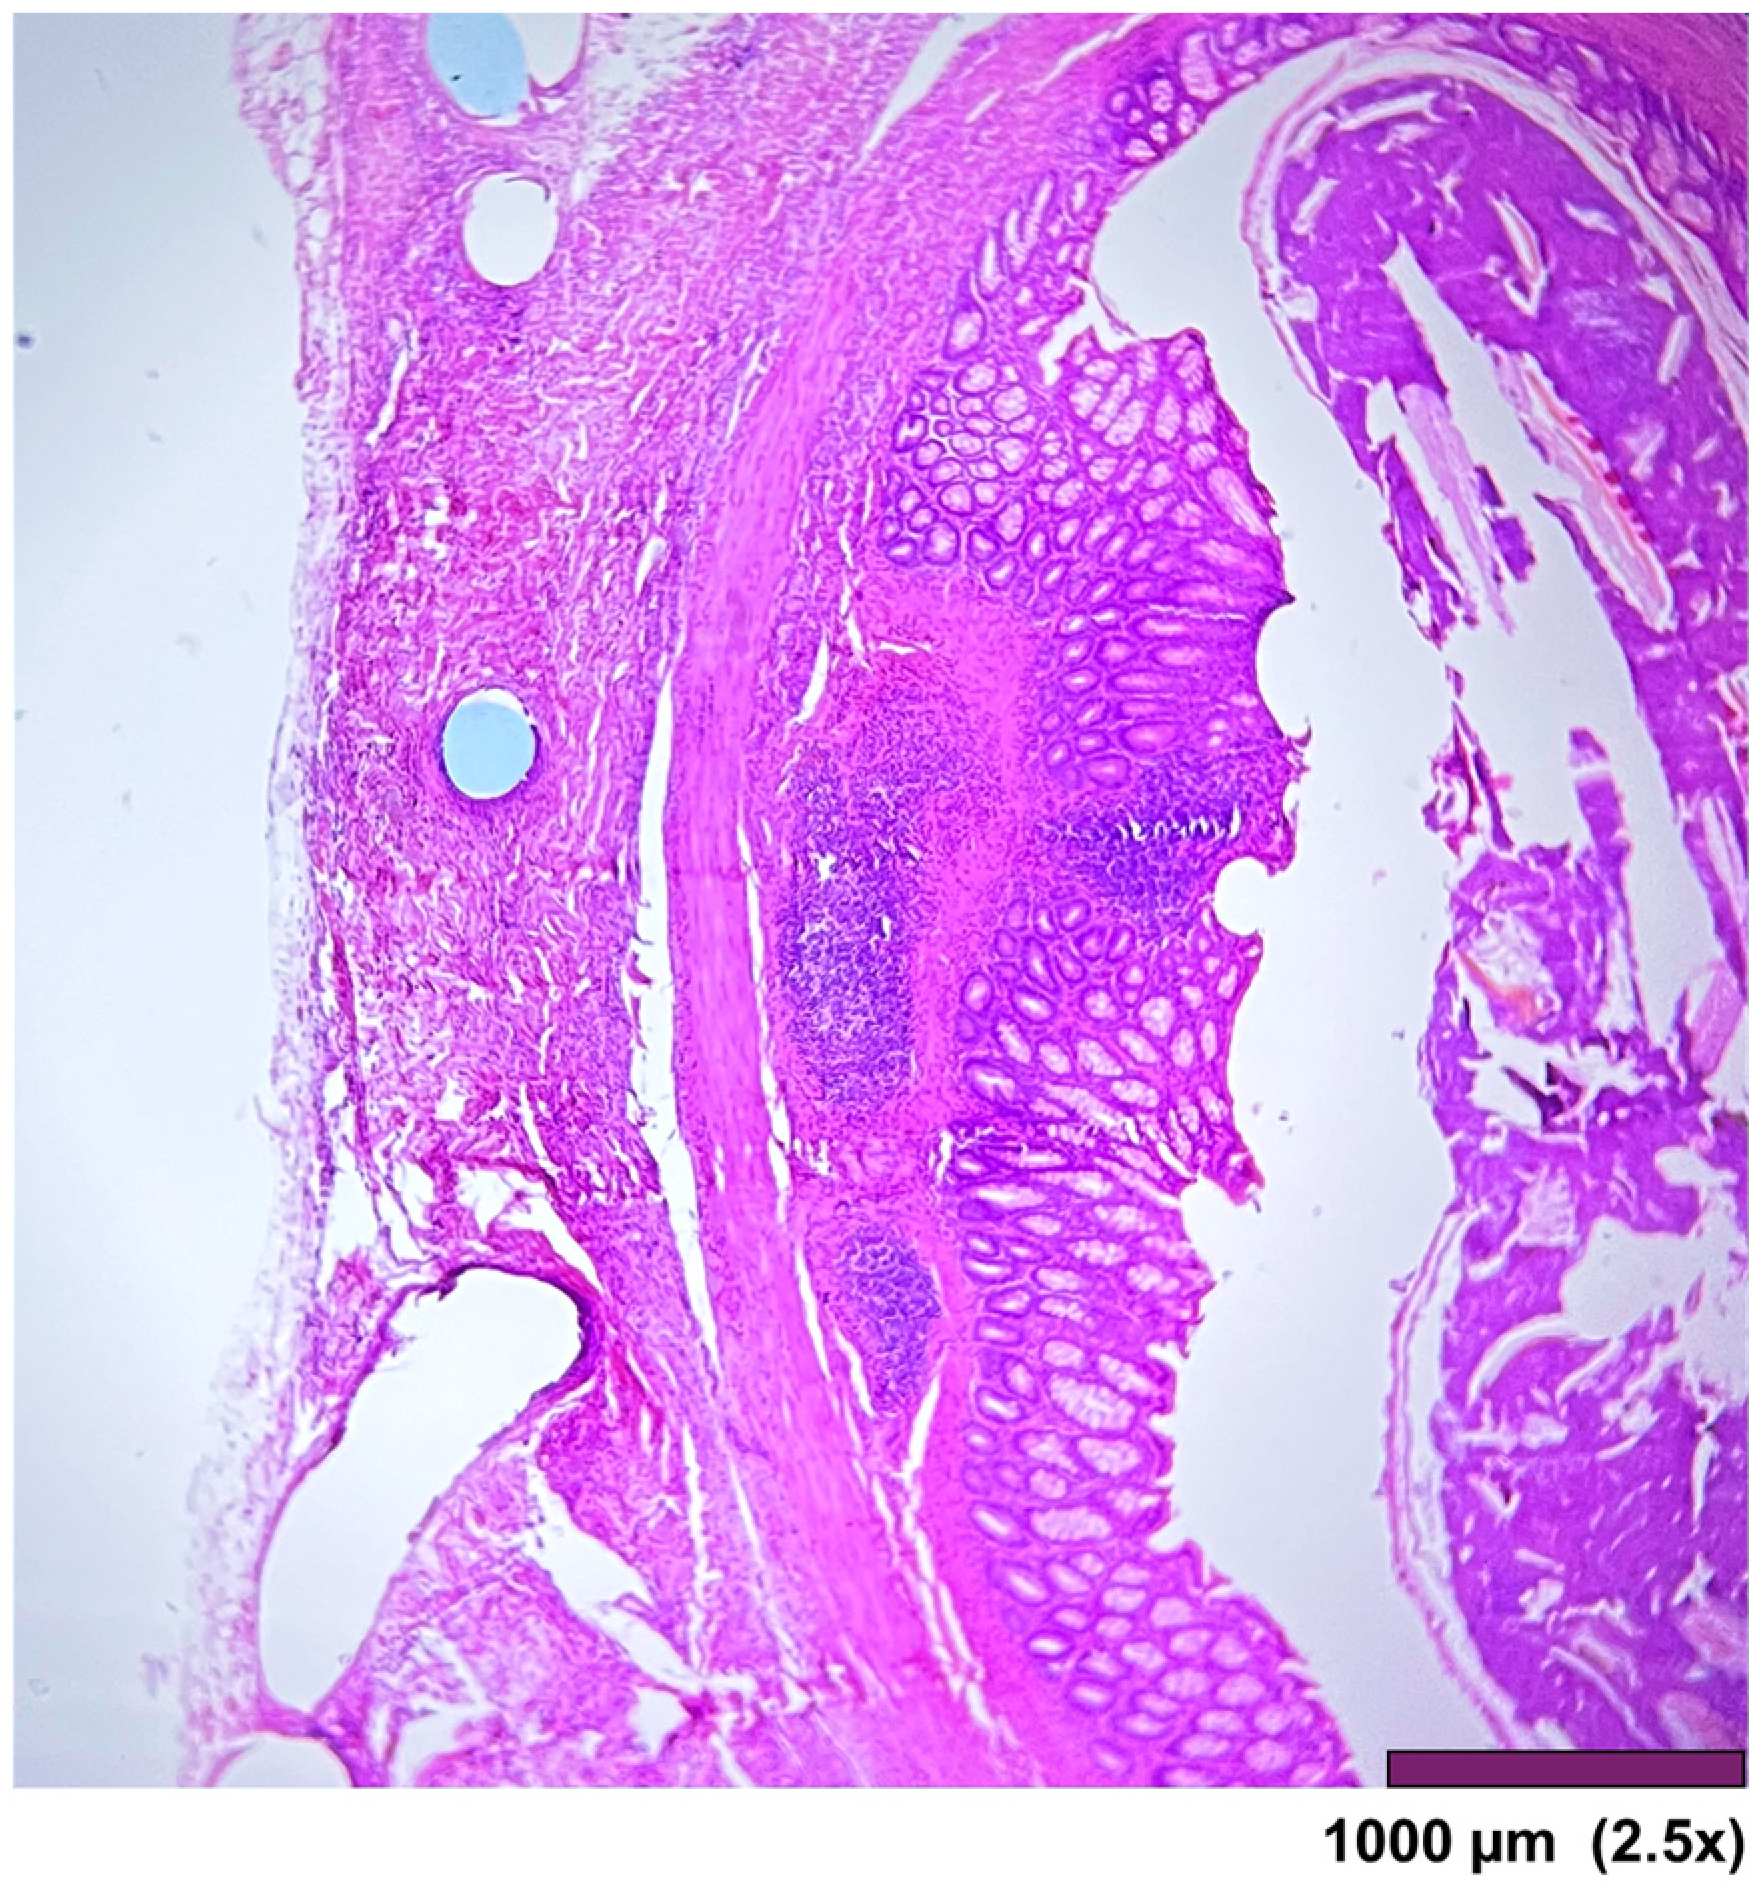

The large intestine wall regenerated completely after surgery, as seen in Figure 9 and Figure 10.

Figure 9. Large intestine: Completely regenerated mucosa, lamina propria, submucosa, muscularis propria, subserosal fat, and granulation tissue with chronic inflammation and foreign body reaction (10×, HE).

Figure 10. Large intestine: mucosa—top layer, submucosa— between mucosa and muscle layer. The mucosal layer completely covers the anastomosis. The holes in the middle are artifacts due to the removal of the anastomotic sutures (2.5×, HE).